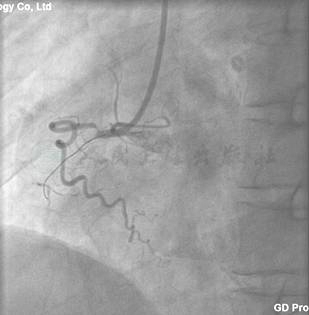

冠状动脉造影结果

LM正常,LAD近端闭塞(图2),LCX轻度动脉粥样硬化(图3),右冠近端完全闭塞(图4)。

图2 LM正常,LAD近端闭塞

图4 右冠近端完全闭塞